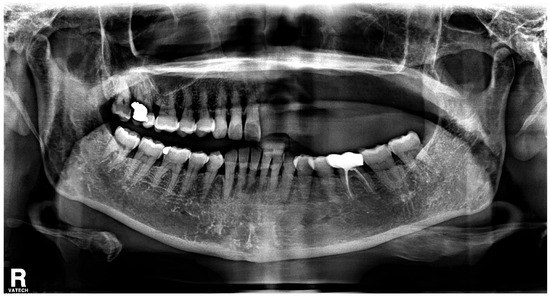

2. Case Report